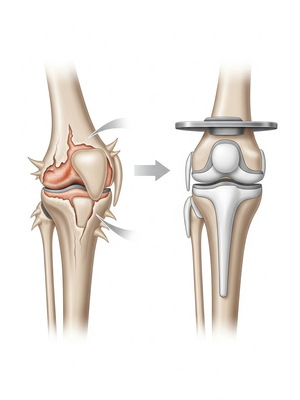

Aşınmış, hasar görmüş ya da eklem yüzeyleri tamamen bozulmuş diz ekleminin, yapay bir eklemle değiştirme işlemidir. Ameliyatta, ağrıya neden olan hasarlı kemik ve kıkırdak dokular çıkarılarak; yerine metal ve özel plastikten yapılmış, uzun ömürlü bir protez yerleştirilir. Bu sayede diz, tekrar ağrısız ve stabil bir şekilde çalışır hale gelir.

Peki total diz protezinde ne yapıyoruz?

Eklem yüzeyleri özel kılavuzlar yardımı ile temizlendikten sonra metal protez eklem yüzeylerine bir kemik çimentosu ile adapte diyoruz. Bu iki metal yüzeyin sürtünmesini azaltmak için polietilenden yapılmış özel bir plastik tabakayı sisteme dahil ediyoruz.